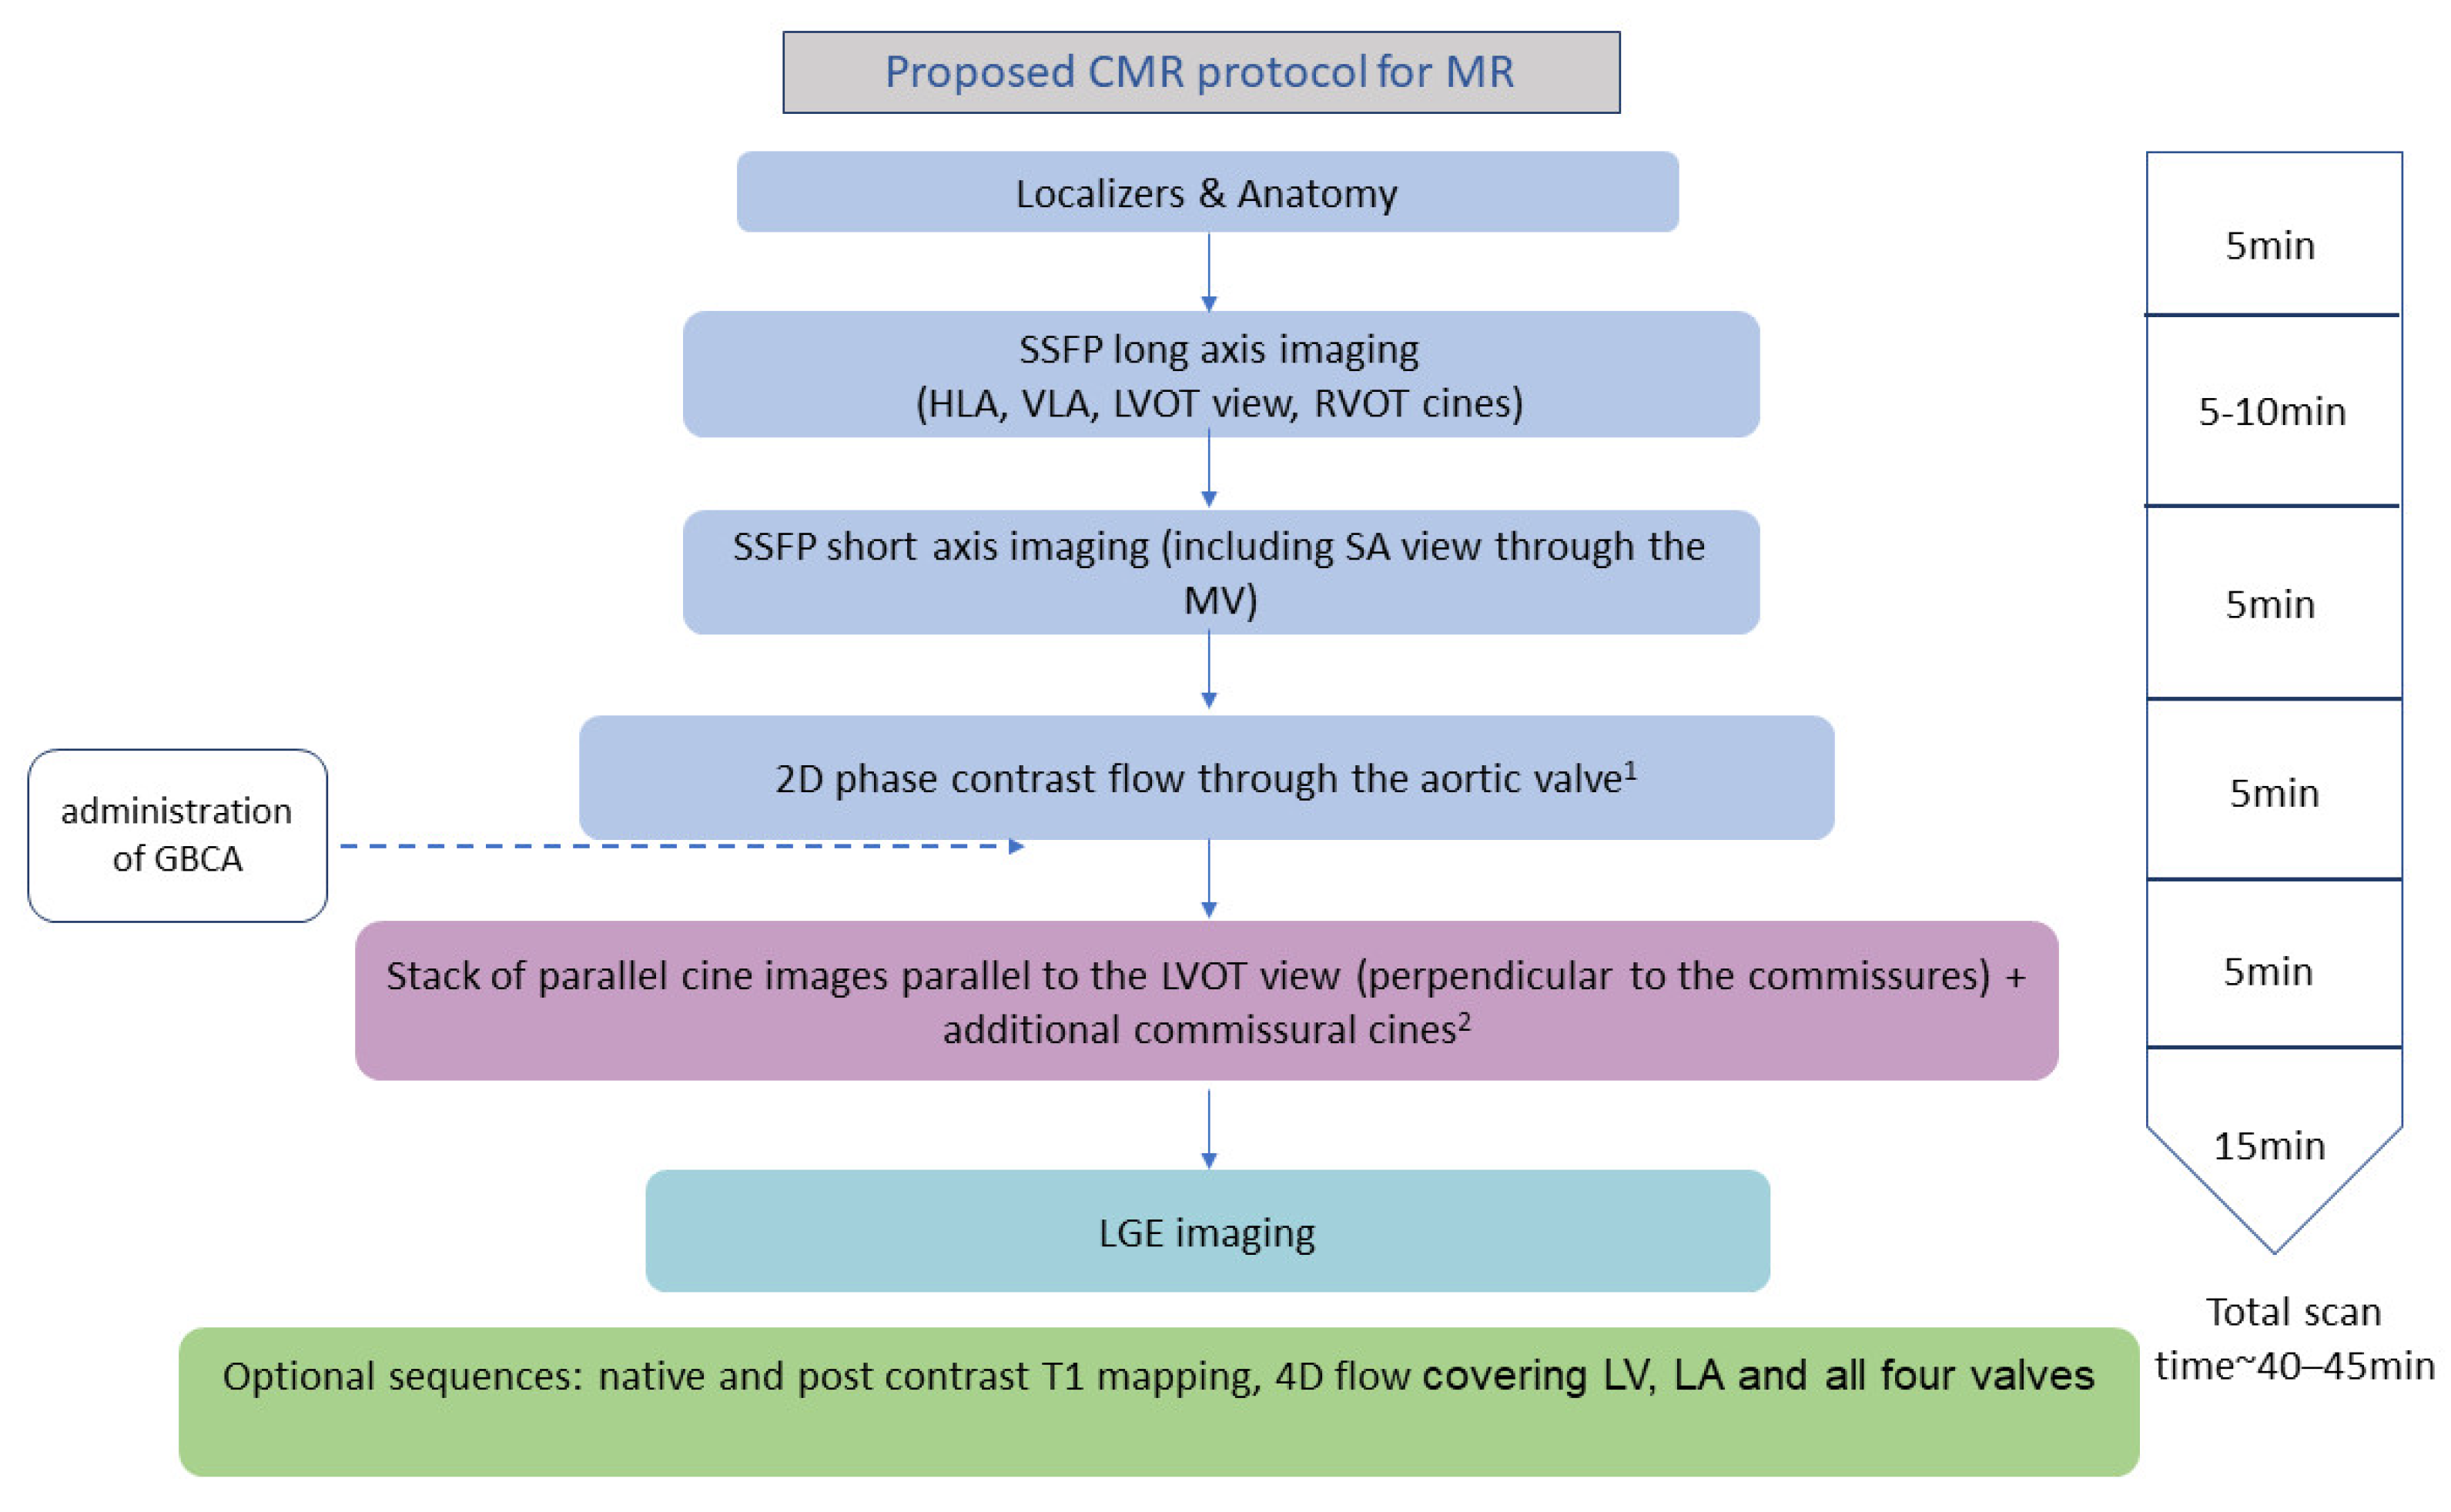

2. How to Assess Mitral Regurgitation with CMR